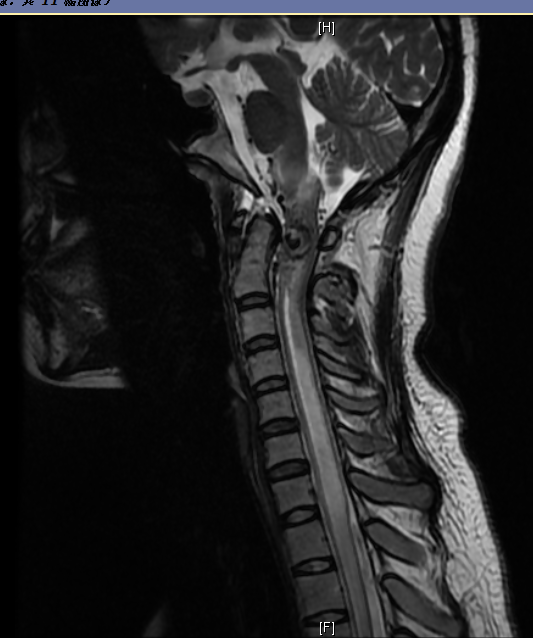

图1:术前MRI提示延髓高颈髓异常出血信号影(蓝色箭头指示)

患者来我院就诊的前一周,突发头痛伴躯体及四肢麻木无力呼吸困难,锁骨以下感觉障碍,排尿障碍。抵京前一天在当地医院行全脑及颈髓血管造影,显示颈椎管内血管性病变,考虑延髓高颈髓血管畸形。考虑到病变高危险情况,当地医院建议来京就诊。“亲手拉扯大的女儿几天功夫就瘫痪了,花样的年华就这样倒下受到无情病魔的困扰……”患者父亲一边叙述患者病情一边深深自责,不禁潸然泪下。